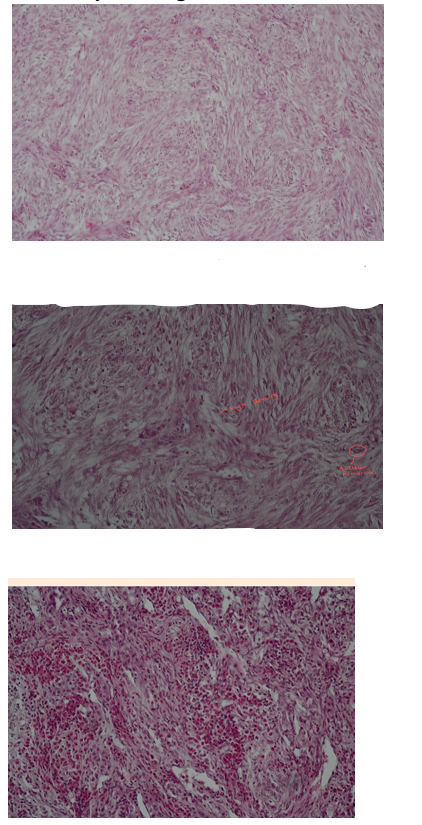

This is?

Fibroma mole - tumor

picture 1: aimlessly running of fibrous fibers, in many directions - felt structure.

pic. 2: miscellaneous differentiation of cells - fibroblast and fibrocytes - small amount of collagen

pic 3: cell infiltrations - heterophils, lymphocytes and macrophages and focal edema